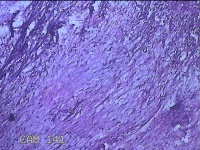

左大腿内侧包块

性别

男

年龄

21岁

临床诊断

脂肪瘤

一般病史

左大腿内侧起包块一月余。

标本名称

大体所见

灰白暗红色包块2.5x2x0.8cm一个,表面糜烂,切开包块呈实性,切面灰白暗红色,质软。

图1

图2